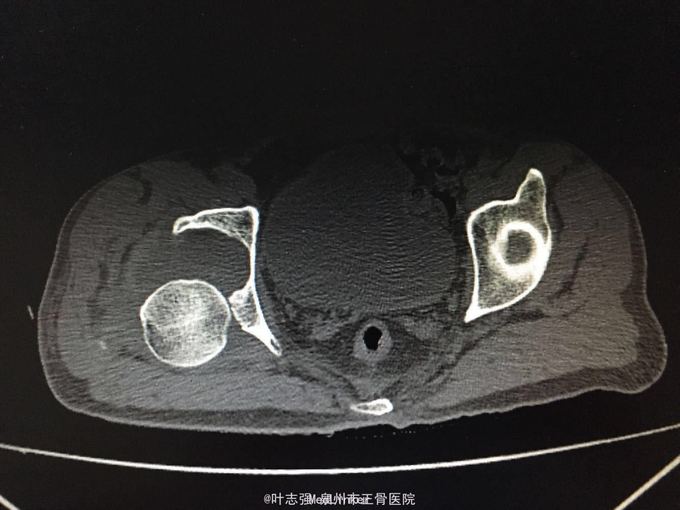

髋臼骨折伴髋关节后脱位ORIF

车祸致左髋部疼痛、活动受限1天。 53岁男性

左髋臼骨折伴髋关节后脱位 行生命支持,股骨髁上骨牵引,